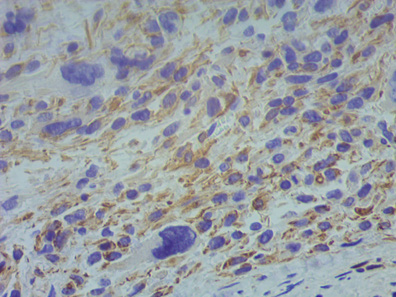

During her postoperative period, course with satisfactory evolution, 3 erythrocyte concentrates and 1 plasma were transfused, after 48 hours a histopathological report is reported with the report of spindle cell variant uterine leiomyosarcoma with tumor site anterior uterine wall and fundus. Figure 1, Figure 2 It is concluded with gynecological oncology in uterine sarcoma EC IB with probable metastasis.

Figure 2 Hematoxylin and eosin staining, with spindle cell neoplasia with a diffuse growth pattern, showing extensive areas of severe nuclear pleomorphism.